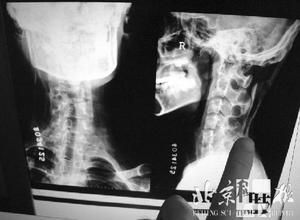

汪國生介紹說,骨化症是一種很奇怪的病,病情很不穩定。國外目前提供的一些治療方法,如骨髓移植、基因療法等都處在實驗研究階段。小麗的病情還在繼續發展,連頸部肌肉都已硬化,難道她真的沒救了嗎?經媒體報導後,國內又一位專家伸出了援助之手,他就是北京中醫藥大學東直門醫院的姜良鐸教授。

據了解,姜教授此前為台灣的一名珊瑚人做過治療,當時小女孩的情況和小麗的情況差不多,雙臂基本不能動,渾身長滿大大小小的硬塊,當時姜良鐸教授也心中無底。整體診斷後,姜教授決定採取將外感病、內傷病結合辨證的方法。服藥3周后,小女孩的疼痛減輕了。2個月後,渾身腫塊就消了一半!據小麗的父親說,目前他們已和姜教授取得聯繫,正在為小麗制訂治療方案。